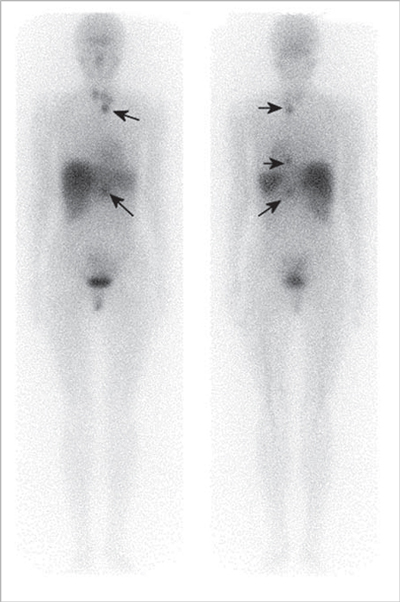

Cáncer medular de tiroides

El tumor medular de tiroides es una neoplasia poco frecuente (3-5% de todos los cánceres de tiroides) proveniente de las células C parafoliculares (Figuras 6 y 7). La mayoría ocurre en forma esporádica (70-80% de los casos) pero existen formas familiares (solos o como parte del síndrome NEM 2A y 2B)20. Este tumor metastiza precozmente a los ganglios cervicales (55-75% de los casos), principalmente el compartimiento central del cuello. Metástasis a distancia se encuentran en 10-15% de los pacientes, principalmente mediastino, pulmones, hígado y hueso21 (Figuras 8 y 9). Debido a la producción de calcitonina por las células C, esta hormona es usada como marcador tumoral al diagnóstico y durante el seguimiento. La resección quir úrgica completa (tiroidectomía total y disección cervical amplia) es la únicaforma de curación. A pesar de la agresividad de este tratamiento, 40% de los pacientes operados mantienen niveles de calcitonina medibles y otro 10% inicialmente negativo, recurrirá en el tiempo2. Por esta razón, la localización de cualquier cúmulo tumoral existente mediante imágenes es de extrema importancia. Los criterios usados en imágenes diagnósticas para el tumor primario son similares a los usados en el cáncer diferenciado de tiroides, sin embargo, la localización de adenopatías y metástasis a distancia es generalmente difícil22. Convencionalmente se ha usado ecografía, tomografía computada y cintigrafía (In111-pentatreotide, Tc99m-DMSA- V y Tc99m-MIBI) para evaluar pacientes con enfermedad recurrente. Tc99m(V)-DMSA (ácido dimercaptosuccínico pentavalente) es un marcador tumoral inespecífico. El mecanismo de captación es sólo parcialmente conocido y tendría relación con la presencia de grupos fosfatos y el pH del medio. Su uso en esta enfermedad fue descrito por primera vez en 1984 por Ohta23. La sensibilidad reportada de la cintigrafía con DMSA-V se encuentra entre 50-80% y su uso combinado con In111- pentatreotide alcanza 86%24. F18-FDOPA es un aminoácido (dihidroxifenilalanina) marcado con Flúor18 usado originalmente para el estudio de pacientes con enfermedad de Parkinson. Los tumores neuroendocrinos pueden captar y decarboxilar p recursores de aminoácidos tales como la DOPA y ser visualizados con PETFDOPA. Las series reportan sensibilidades entre 44 y 90% para este método2. Desafortunadamente para la síntesis de F18-FDOPA se requiere de blancos especiales en el ciclotrón (diferentes a los usados para la producción de FDG) y de módulos de síntesis dedicados, lo que hace que este radiofármaco aún no esté disponible en nuestro medio. Si bien el 85% de los tumores medulares de tiroides expresan algún tipo de receptores de somatostatina y 75% expresan los tipos 2,3 ó 5 (que son los afines por octreotide), el subtipo 2 es expresado sólo en 43%25, que es el blanco principal de los análogos disponible para imagen y terapia. La afinidad de estas moléculas por los subtipos 3 y 5 es típicamente menor. Esto explica la variabilidad de resultados en la literatura en relación con la sensibilidad tanto de la cintigrafía con In111-pentatreotide (Octreoscan) como para el PET con derivados de la somatostatina para la detección de esta neoplasia. Las series publicadas con In111-pentatreotide reportan sensibilidades entre 50-75% para cáncer medular de tiroides y sugieren que este método es mejorpara metástasis ganglionares en el cuello o mediastino que para metástasis a distancia2. Estudios con PET y análogos de somatostatina son escasos para esta enfermedad. La limitada información disponible sugiere que la sensibilidad de PET-análogos de somatotatina es inferior al PET-FDOPA en cáncer medular de tiroides tanto a nivel de paciente como de lesión y similar a los resultados de estudios realizados con PET-FDG. En el trabajo retrospectivo de Conry et al2, se estudiaron 18 pacientes con recidiva de cáncer medular de tiroides a los que se le realizó PET con Ga68-DOTATATE y F18-FDG. La sensibilidad encontrada por paciente fue 72% para DOTATATE y 78% para FDG. FDG encontró 28 metástasis mientras que DOTATATE 23. Treglia et al26 recientemente publicó una serie prospectiva de 18 pacientes con recurrencia de cáncer medular de tiroides estudiados PET y Ga68-análogos de somatostatina, F18-FDOPA y F18-FDG. En este trabajo la sensibilidad por paciente fue 72% para FDOPA, 33% para análogos de somatostatina y 17% para FDG. A nivel de lesiones la sensibilidad fue: 85% para FDOPA, 20% para análogos de somatostatina y 28% para FDG.